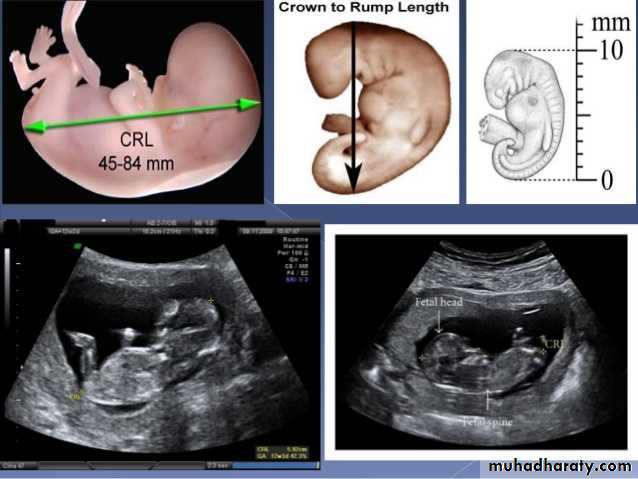

Mosul Medical College /radiology department2016BPD together with head circumference (HC), abdominal circumference (AC), and femur length (FL) are computed to produce an estimate of fetal weight. In the second trimester this may be extrapolated to an estimate of gestational age and an estimated due date (EDD) .